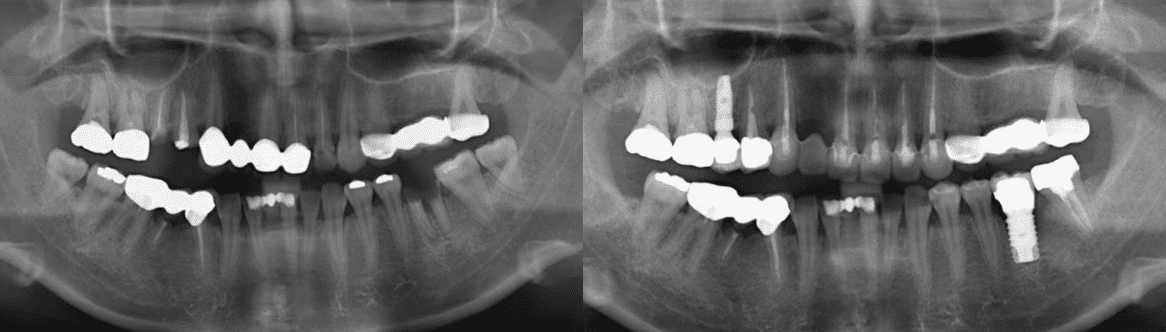

한꺼번에 많은 치아를 발치하고 여러개의

임플란트를 심는 경우부터 간단한 스케일링까지